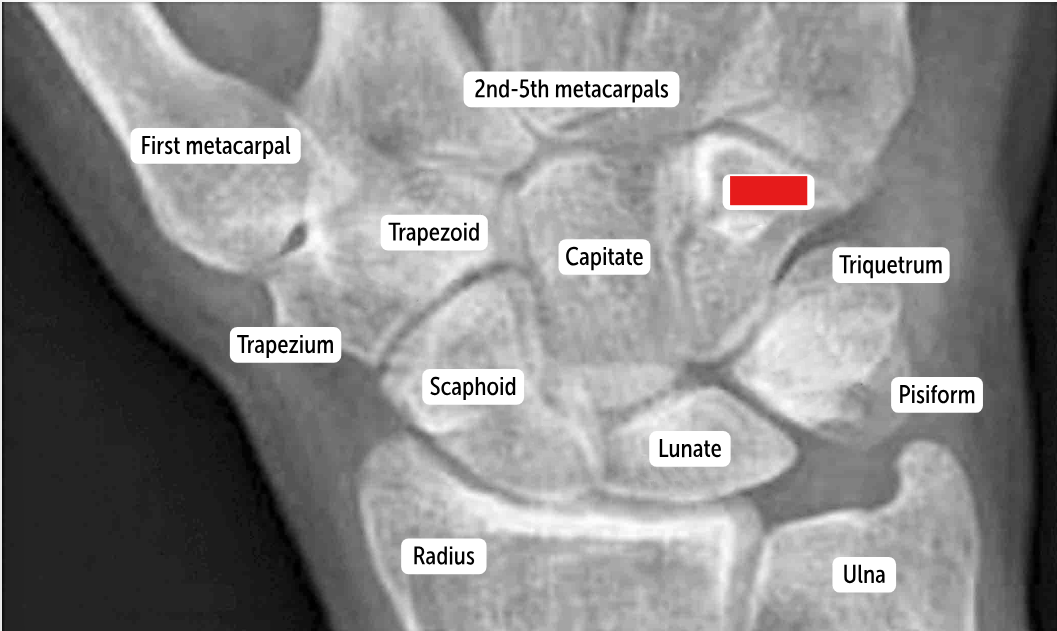

Carpal bones by row:

So Long To Pinky, Here Comes The Thumb

Scaphoid, Lunate, Triquetrum, Pisiform, Hamate, Capitate, Trapezoid, Trapezium

Scaphoid

Lunate

Triquetrum

Pisiform

Hamate

Capitate

Trapezoid

Trapezium